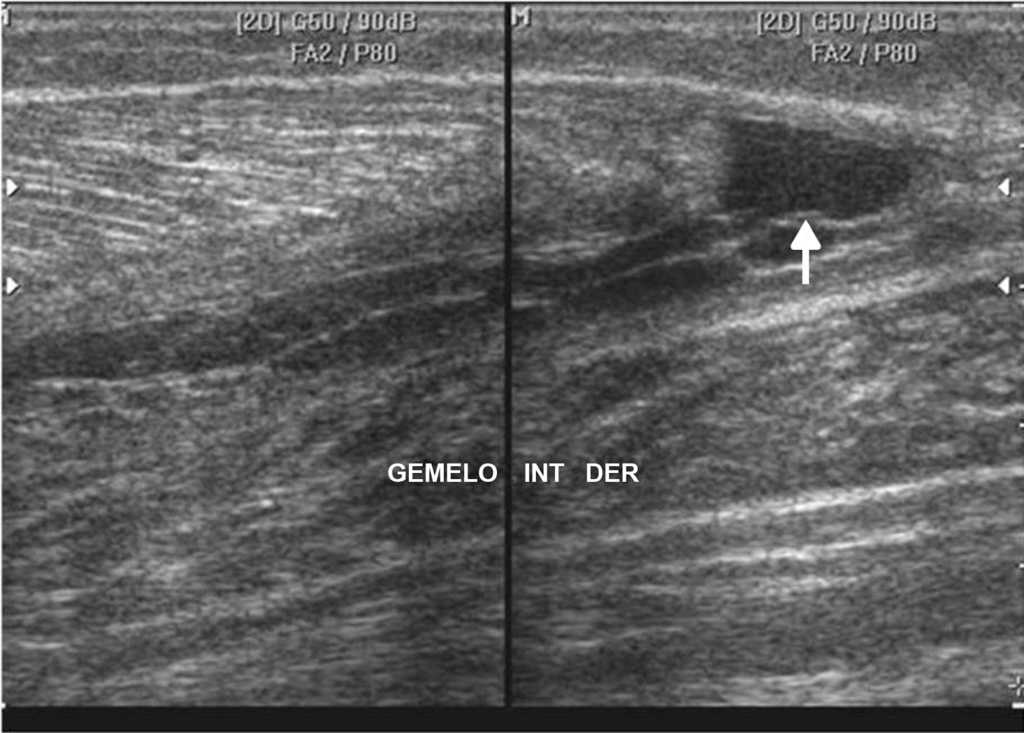

La ecograf??a es el m??todo ideal para la exploraci??n del sistema musculoesquel??tico, en tanto brinda la posibilidad de evaluarlo en reposo o en movimiento, observando los cambios en tiempo real. Adem??s, permite la comparaci??n del sitio exacto del dolor con su lado contralateral, adquiriendo im??genes en panor??mica19.

Los actuales transductores de alta frecuencia (12-18 MHz) tienen excelente resoluci??n para analizar las estructuras superficiales (m??sculos, tendones, ligamentos y bursas) y sus patolog??as20 (figs. 14 y 15). La ecograf??a en escala de grises permite una gran imagen anat??mica de la lesi??n, mientras que el Doppler color identifica la vascularizaci??n del tejido y las im??genes panor??micas otorgan una visualizaci??n extensa del campo de visi??n, que muestra la lesi??n y su relaci??n con las estructuras vecinas (fig. 16).